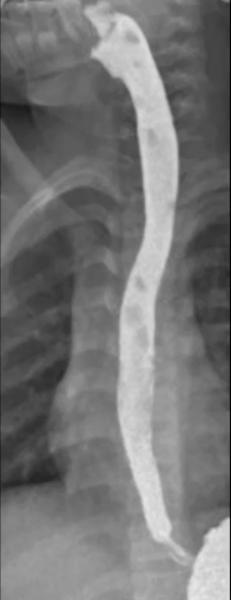

Permeabilidad postoperatoria

EVDA y seriada de control: paso libre a cámara gástrica, ausencia de extravasación; estos son criterios de integridad anastomótica/rafia y resolución de la obstrucción.

Engrosamiento residual discreto en cara posterior cervical

En la seriada de seguimiento, leve engrosamiento mural posterior a nivel de escotadura supraesternal, sin estenosis ni retención, compatible con cambios cicatrízales posquirúrgicos; la recurrencia de quistes es rara tras resección completa, pero el control imagenológico es recomendado.